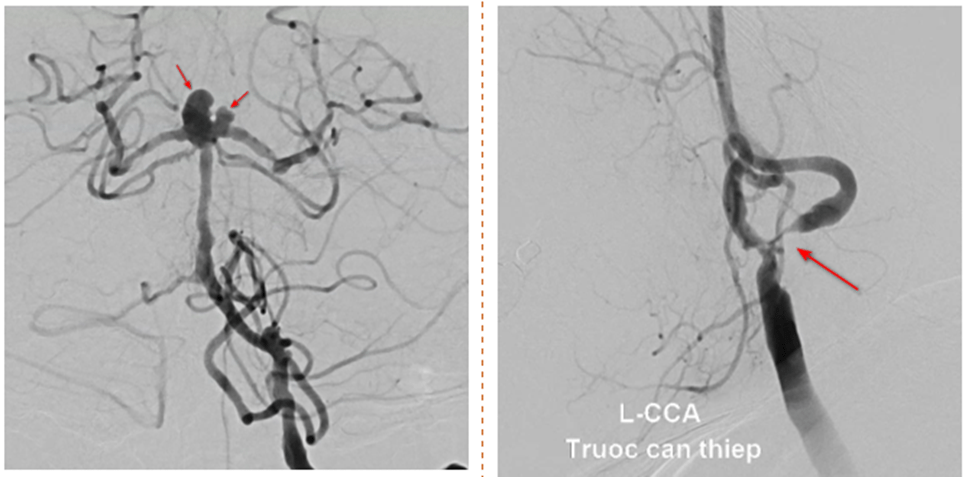

Điều bất ngờ là mặc dù triệu chứng của bà M. là nhồi máu não, nhưng sau khi chụp MRI các bác sĩ lại phát hiện thêm nguy cơ xuất huyết não do phình mạch còn nguy hiểm hơn. Kết quả chụp MRI não thấy rõ tổn thương hẹp gốc động mạch cảnh trong 2 bên và túi phình đỉnh động mạch thân nền và động mạch tiểu não sau dưới, với kích thước là 4.5x5mm và 3x3mm, trên nền nhồi máu cơ tim cũ đã stent, tăng huyết áp, thiếu máu mạn mức độ trung bình – bệnh thận mạn giai đoạn 3 có những đợt cấp tái phát.

Qua hội chẩn, các bác sĩ đưa ra phương pháp điều trị tối ưu cho túi phình cổ rộng, đỉnh động mạch thân nền của bà M. chính là đặt stent kết hợp thả coil. Tuy nhiên do bà M. cần sử dụng thuốc chống kết tập tiểu cầu nên nguy cơ vỡ túi phình đỉnh động mạch thân nền là rất cao.

Điểm khó ở bệnh nhân này chính là tổn thương hẹp nặng động mạch cảnh trong trái và túi phình xảy ra cùng lúc nên điều trị cần triệt để cho cả 2 vấn đề.

Về túi phình thì rất khó để can thiệp nội mạch dẫn đến phải sử dụng stent để hỗ trợ quá trình đặt coil giúp coil giữ ổn định trong lòng túi phình, một kỹ thuật khó trong can thiệp nội mạch.”